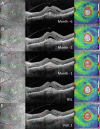

Methods: Patients with recalcitrant nAMD were switched to brolucizumab therapy. Functional and structural parameters 4 weeks after first brolucizumab injection were evaluated including best-corrected visual acuity (BCVA (logMAR)), foveal centre point (FCP (µm)), central subfield retinal thickness (CSRT (µm)) and macular volume (mm³).

Results: Sixty-three eyes of 57 patients with nAMD (52.6% females) with a mean (±SD) age of 79.5±6.7 years were included. Mean change of BCVA was 0.03±0.14 logMAR (p=0.115). Significant reductions were recorded for FCP with a mean (±SD) change of -66.81±72.63 µm, -66.76±60.71 µm for CSRT and -0.27±0.24 mm³ for macular volume (all p<0.001). Intraocular inflammation was observed in seven eyes of seven patients, including one case of retinal vasculitis.